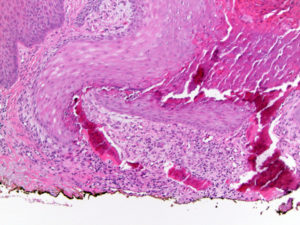

Для выявления остеомы требуется провести гистологическое исследование увеличенной ткани

В данном случае необходимо исключить злокачественные опухоли, деформации из-за рахита и полиомиелит. Первоначальное обследование выполняется с применением рентгенографии или компьютерной томографии

Исследование гистологического образца удаленной остеомы лобной кости обязательно проводится.

При изучении остеоидной остеомы под микроскопом обнаруживается остеогенная ткань, содержащая большое количество сосудов. Центральная область опухоли представлена участками формирования и разрушения костной ткани с извилистыми балочками и пластинами. В зрелых опухолях можно наблюдать области склерозирования, а в «старых» опухолях — области настоящей волокнистой кости.